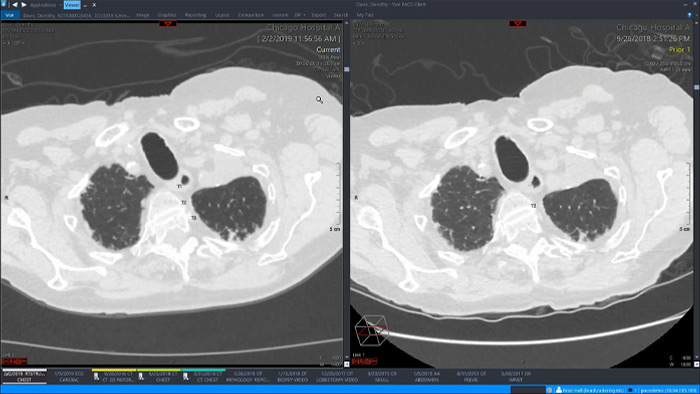

Analicemos algunos de los beneficios inmediatos de un enfoque unificado. Un espacio de trabajo único y unificado para radiología incorporaría funciones avanzadas de posprocesamiento 3D y distribución de imágenes, que se abrirían en un visor adicional para facilitar el trabajo.

Mediante un espacio de trabajo unificado, los usuarios podrían iniciar fácilmente las herramientas de análisis pertinentes desde las más de 70 aplicaciones avanzadas disponibles en varios dominios clínicos. La inteligencia artificial puede desempeñar un importante papel a la hora de automatizar las tareas y flujos de trabajo y predecir los patrones de uso.

Por qué necesita un espacio de trabajo todo en uno

Un espacio de trabajo unificado y completamente integrado en la plataforma de adquisición de imágenes empresarial y en el visor de diagnóstico, ofrece un acceso sencillo y eficaz a todas las herramientas necesarias en todos los ámbitos clínicos. El acceso con un solo clic a herramientas de visualización avanzadas, como la colonoscopia virtual, el procesamiento 3D y la adquisición de imágenes espectrales, permite una interpretación eficaz y aumenta la fiabilidad del diagnóstico.

Ofrece funciones de visualización avanzada con un sólido conjunto de herramientas para la evaluación cuantitativa asistida por IA y la generación automática de resultados.